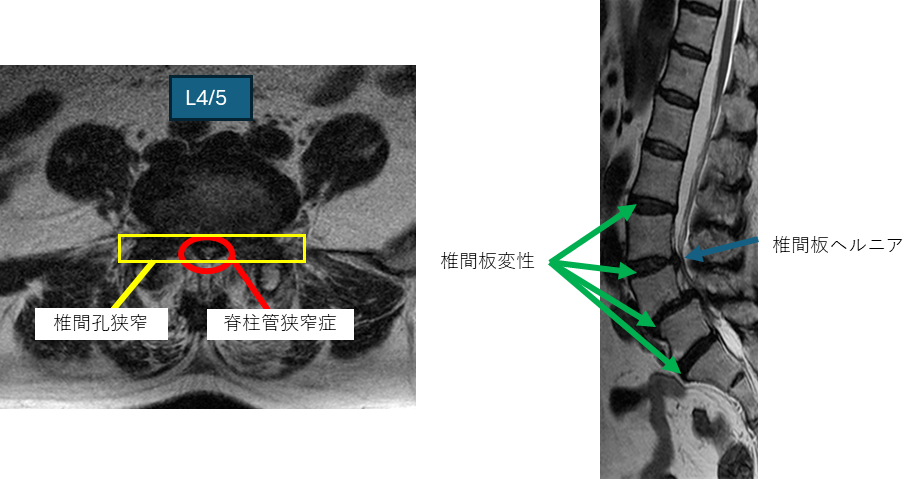

画像及び所見について

L1/2: 異常なし

L2/3: 椎間板変性症

L3/4: 椎間板変性症、椎間板ヘルニア

L4/5: 椎間板変性症、すべり症、脊柱管狭窄症、椎間孔狭窄

L5/S: 椎間板変性症

以上の事が画像上認められます。

L2/3,3/4,4/5,5/sに

椎間板変性症,脊柱管狭窄症を認め、主症状の原因の可能性が高い。